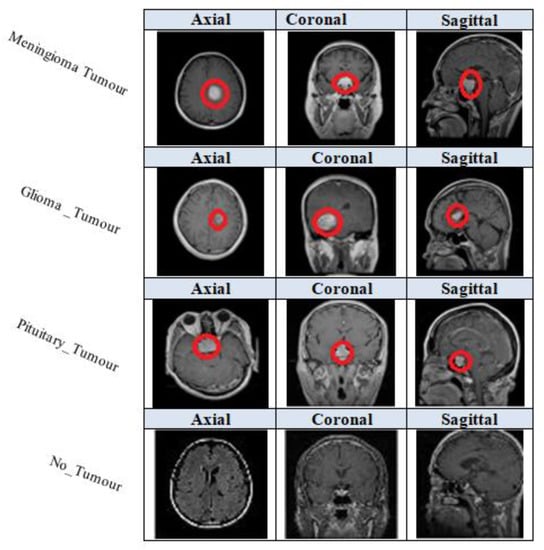

4.1. Dataset